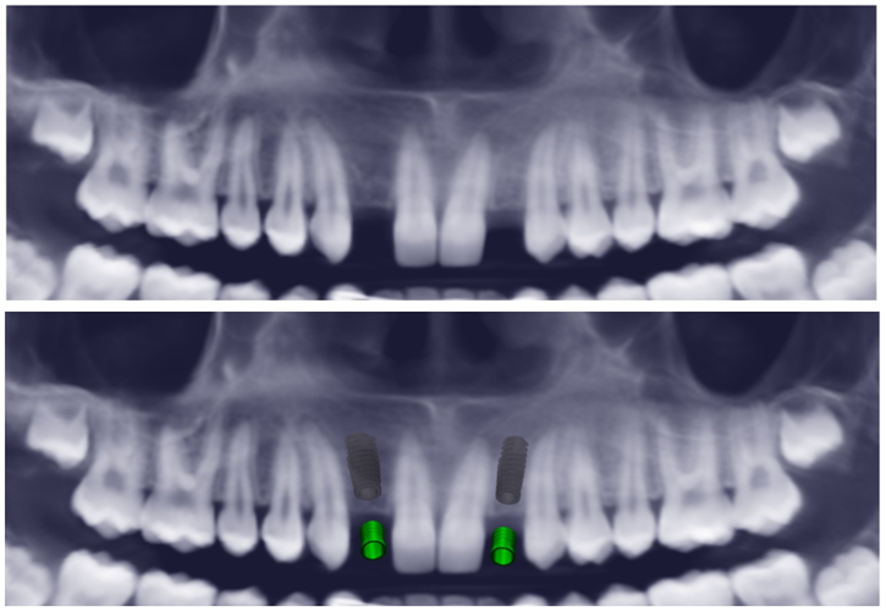

Foi feita a avaliação clínica, radiográfica e exames complementares para delinear o plano de tratamento que consiste em instalação de implantes e coroas sobre implantes devido a agenesia no 12 e 22. Além disso, a paciente possui erupção passiva alterada associada ao sorriso gengival, portanto seria necessário a realização da gengivoplastia em todos os dentes anteriores superiores. Havia ainda indicação de clareamento dental. Todo o planejamento cirúrgico foi realizado por meio da tomografia com o software Blue Sky Plan® (Blue Sky Bio-Libertyville, Illinois, EUA).

A projeção tridimensional do trabalho foi realizado com o CAD/CAM®, com o planejamento do implante e da prótese. Isso garante a previsibilidade da etapa cirúrgica e protética, bem como as posições ideais e angulações favoráveis.

Em ambos os dentes, 12 e 22, foi planejado o implante da Implacil De Bortoli – Due Cone – Maestro CM Pilar Digital 3.8 Ø 3.5 mm X 11 mm. Esse implante possui câmaras de cicatrização, ideal para carga precoce, e a cirurgia foi realizada com uma guia cirúrgica para maior efetividade da reprodução do planejamento.